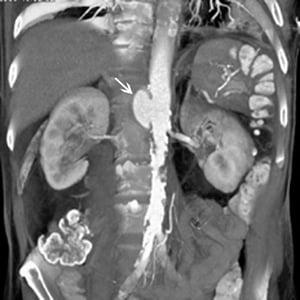

Pseudoaneurisma dell'aorta addominale (TC)

La freccia bianca mostra uno pseudoaneurisma dell'aorta addominale soprarenale. Vi è anche un'ampia placca nell'aorta sottorenale e le arterie iliache.

© 2017 Elliot K. Fishman, MD.